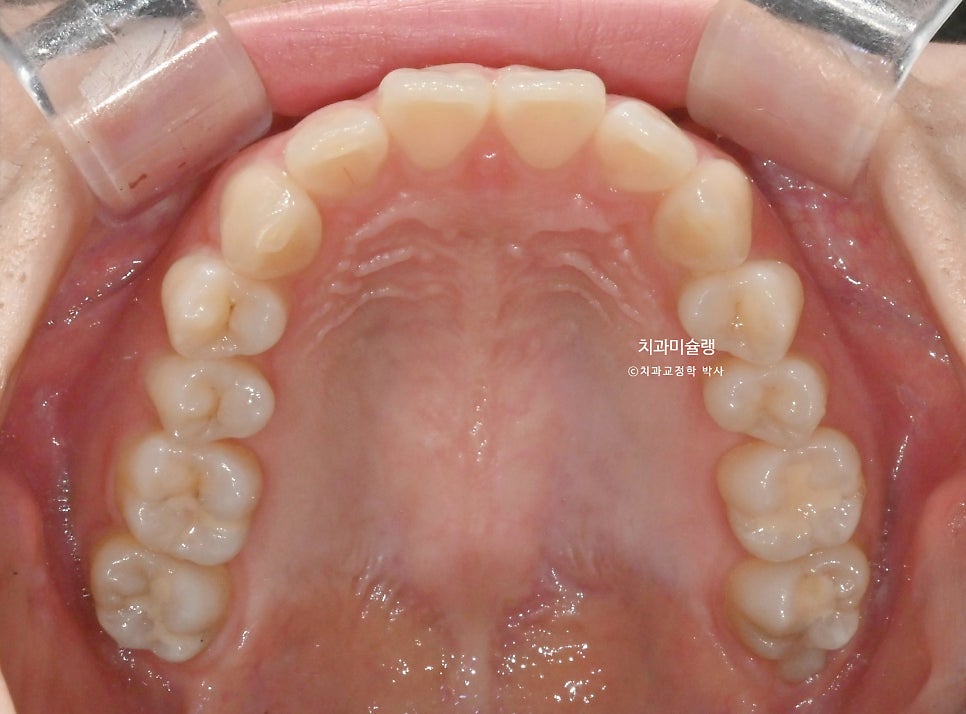

25년 6월부터 10월까지, 3개월 반에 걸쳐 14개 장치를 모두 낀 후 모습입니다.

과개교합이, 중심선, 배열의 개선이 보입니다.

어금니 교합은 1급 교합관계를 보이며

배열과정에서 생긴 블랙트라이앵글을 소량 줄이기 위해 추가장치 제작에 들어갔고 2026년 3월, 드디어 치료를 마무리 합니다.

어금니 교합은 물샐틈 없는 1급 교합관계를 보입니다.

작은어금니 회전까지 완벽 개선되었습니다.

안으로 쓰러져 있던 위 송곳니각도가 개선되었습니다.